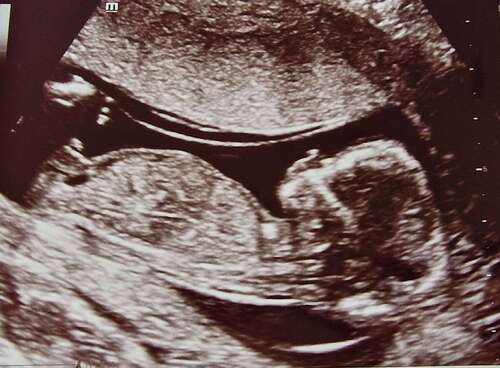

Hi, deze echo is van 13+1, is hier een nub op zichtbaar?

Volgens mij ligt het beentje voor. Maar weet het niet zeker. Denk een 🩷